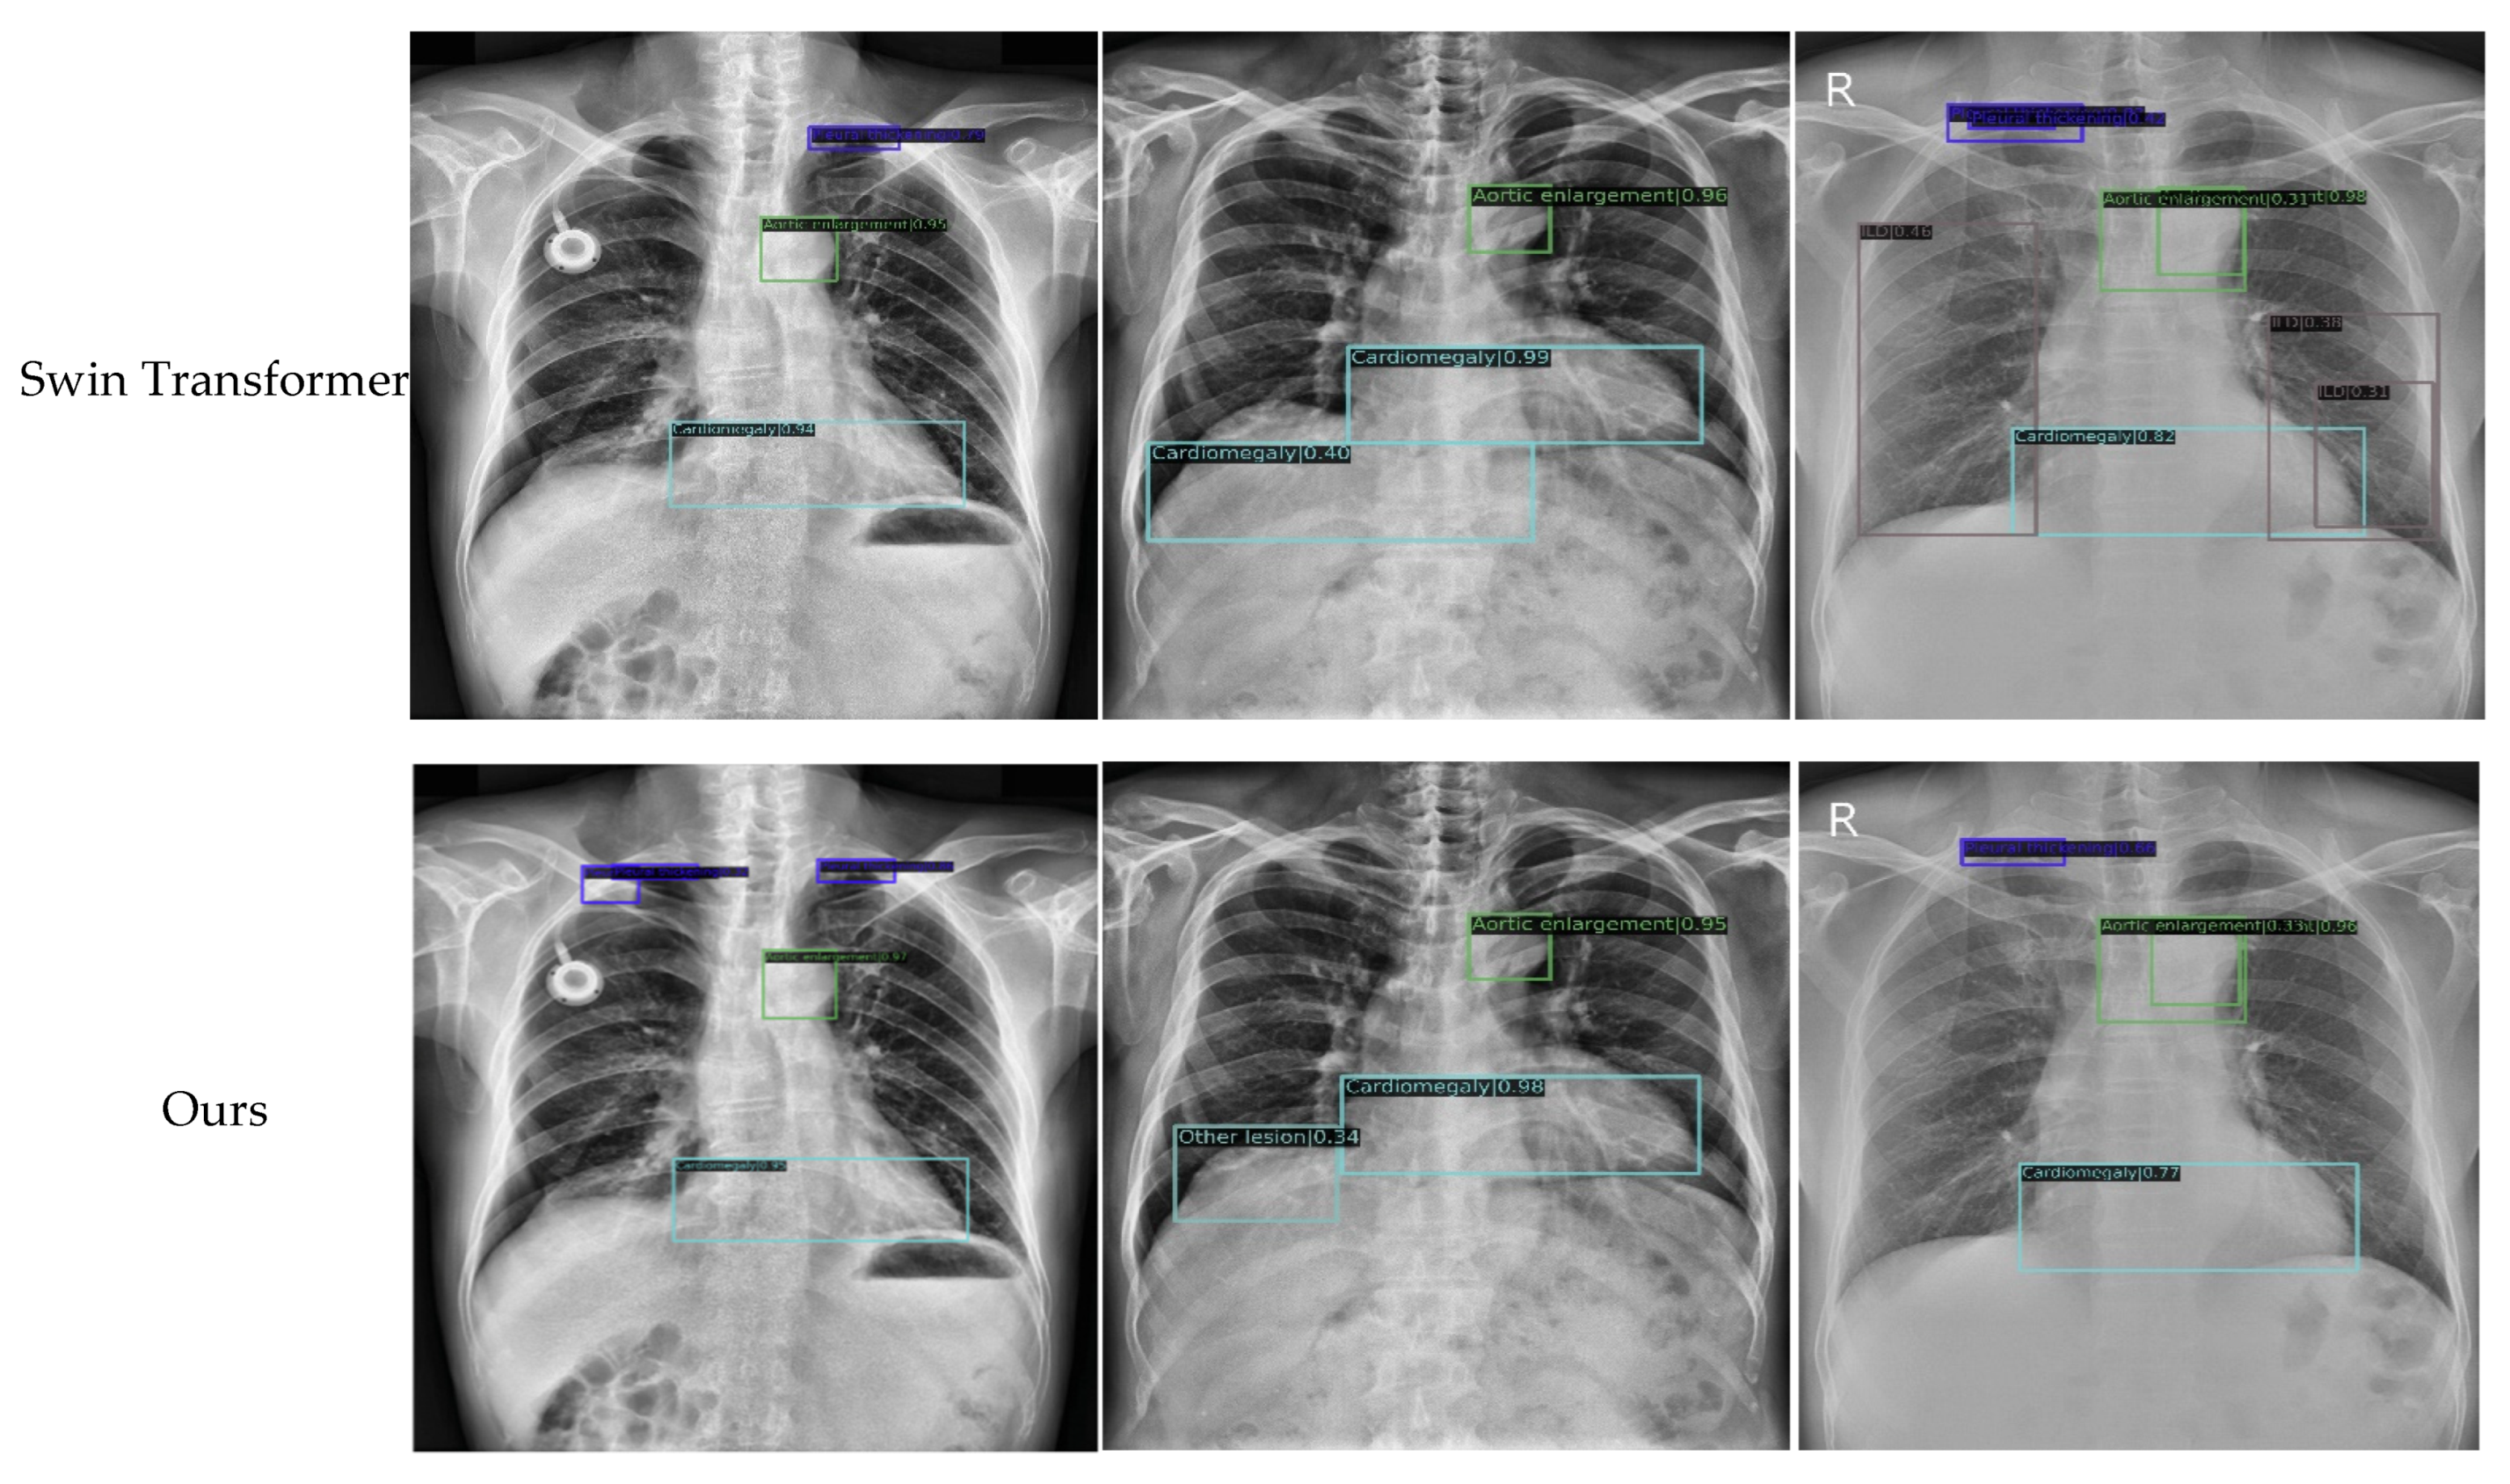

4.3. Comparison with the Latest Methods